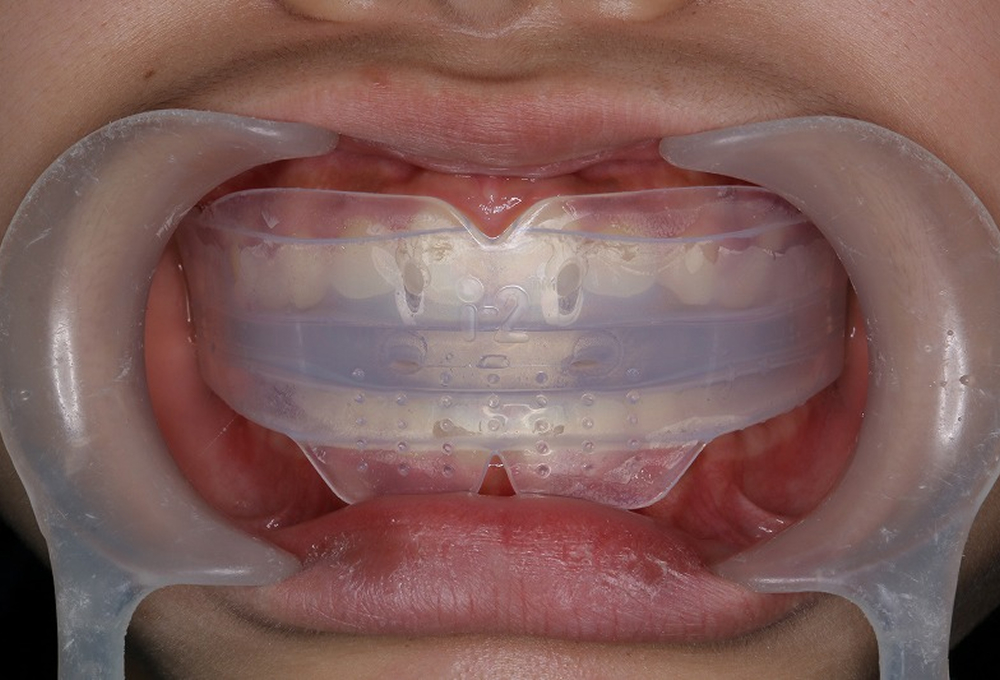

④トレーナー使用